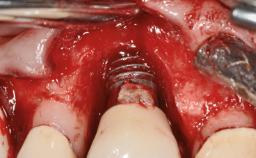

A 65-year-old female patient was referred to the periodontist for assessment and management of implant site 12. Implant 12 had been placed ten years previously and restored with a cemented single crown. The patient was a non-smoker in good general and periodontal health. On examination there were 7 mm probing depths at implant 12 with suppuration and bleeding on probing. The patient was aware of the presence of pus but had no discomfort. A periapical radiograph showed marginal bone loss to approximately the third thread of the implant. Previous radiographs obtained from the referring clinician indicated that there had been progressive bone loss since the implant was restored. A diagnosis of periimplantitis was made.